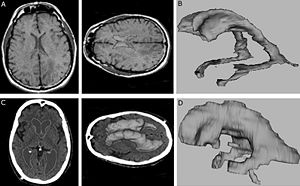

- 4.9 A New Improved Method for Assessing Brain Deformation after Decompressive Craniectomy

- 4.23 Bi-modal Non-rigid Registration of Brain MRI Data with Deconvolution of Joint Statistics